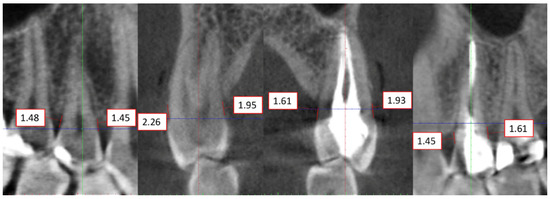

2.4. Radiographic Examinations

2.5. Evaluation of Radiographs